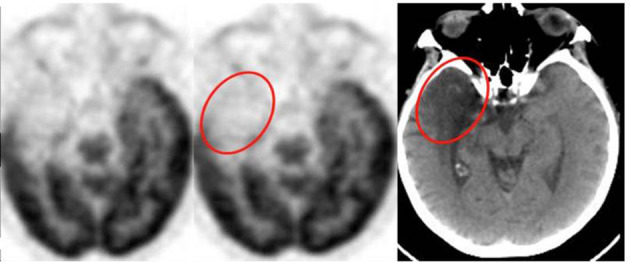

La Demenza a Corpi di Lewy (DLB) e il “Cingulate Island Sign“

La DLB si manifesta spesso con ipometabolismo parieto-occipitale, simile alla PCA, ma con una distinzione fondamentale riguardante il cingolo posteriore.

Cingulate Island Sign (CIS): si riferisce alla relativa preservazione del metabolismo nella corteccia cingolata posteriore nonostante il marcato ipometabolismo nel precuneo e nelle aree occipitali circostanti.18

Il CIS ha una specificità estremamente elevata (fino al 100% in alcuni studi) per la DLB rispetto all’AD, dove il cingolo posteriore è tipicamente una delle prime aree a diventare ipometaboliche.19